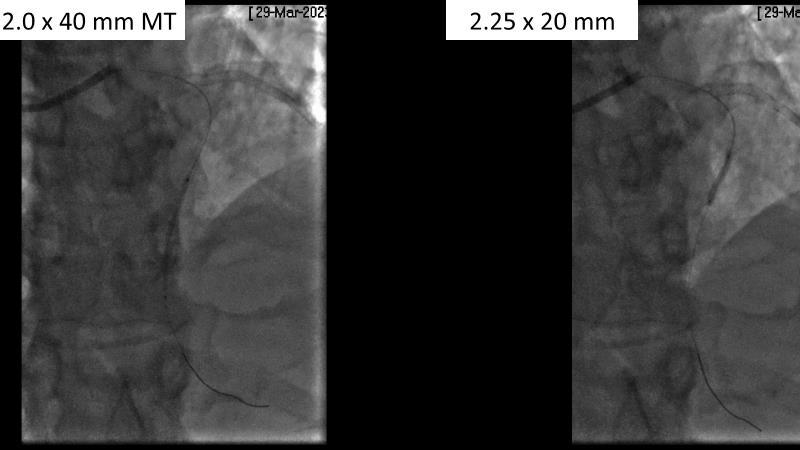

Sirolimus-coated balloon: exploring the case- and clinical-based evidences

Browse this EuroPCR 2024 session to explore the safety and efficacy of sirolimus-coated balloons from pre-clinical data, review MagicTouch data from real-world populations with case-based examples, and learn about the MagicTouch sirolimus-coated balloon clinical programs. Discover insights and takeaways from the significance of the EASTBOURNE subgroups, and analyze the challenges and opportunities in PCI for diabetic patients.

- To learn from the real world registries and complex cases to understand the practical implications and potential of the device in diverse patient population